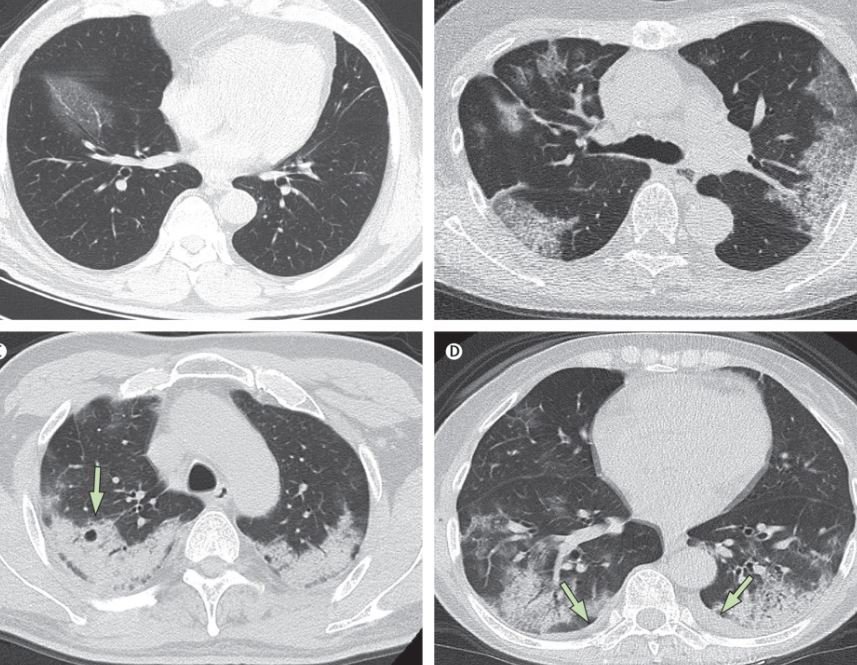

- Khảo sát đặc điểm, vị trí, kích thước, mật độ của các tổn thương bệnh lý ở phổi, trung thất, thành ngực.

- Phát hiện vị trí, kích thước, mật độ của tổn thương;